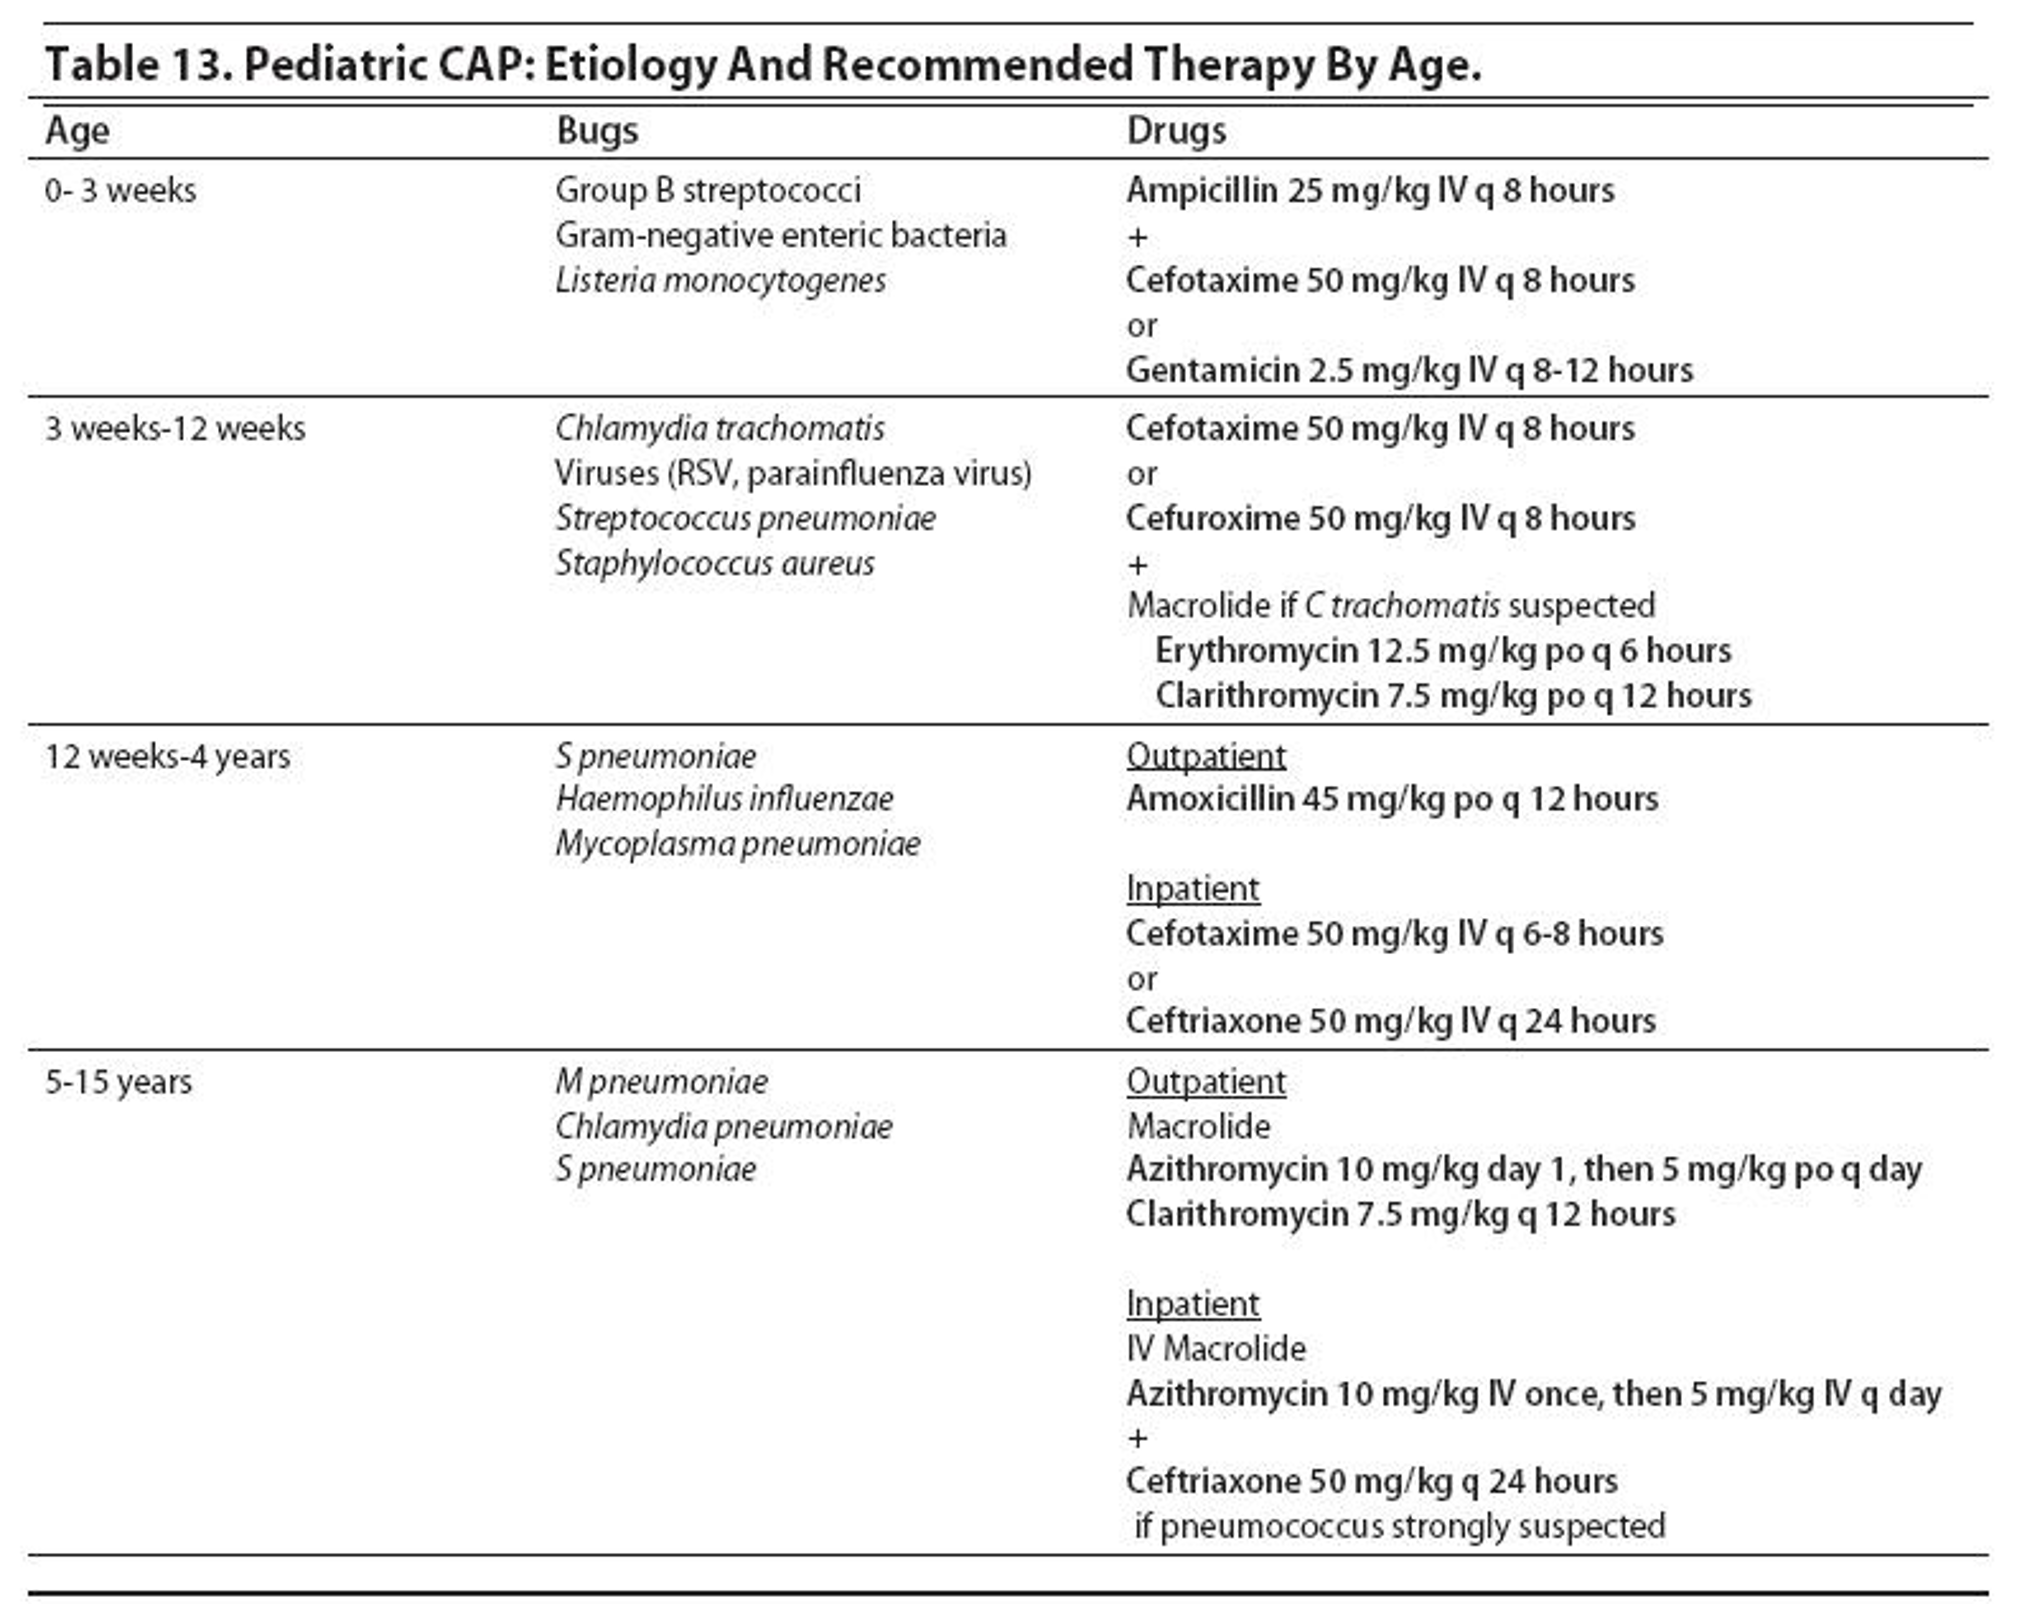

TREATMENT

As viral and bacterial pneumonia are often difficult to distinguish, treatment including the use of antibiotics is based on age and severity. Treatment may include:

- Antibiotics:

- Outpatient

- <5 years: amoxicillin is the first choice oral antibiotic, alternatives include co-amoxiclav and macrolides

-

5 years: a macrolide (erythromycin, clarithromycin, or azithromycin) is the first choice oral antibiotic as mycoplasma infection is more likely.

- Hospital

- Oral antibiotics are safe and effective for many children with CAP, but in severe cases with sepsis, consolidation with effusion, failed response, or intolerance to oral antibiotics, IV treatment is indicated with a third-generation cephalosporin (e.g., cefotaxime, ceftriaxone) or ampicillin.

- A change to oral antibiotics can then be made if there is clear improvement.

- Treatment duration is between 5 and 10 days depending on severity.

- Outpatient